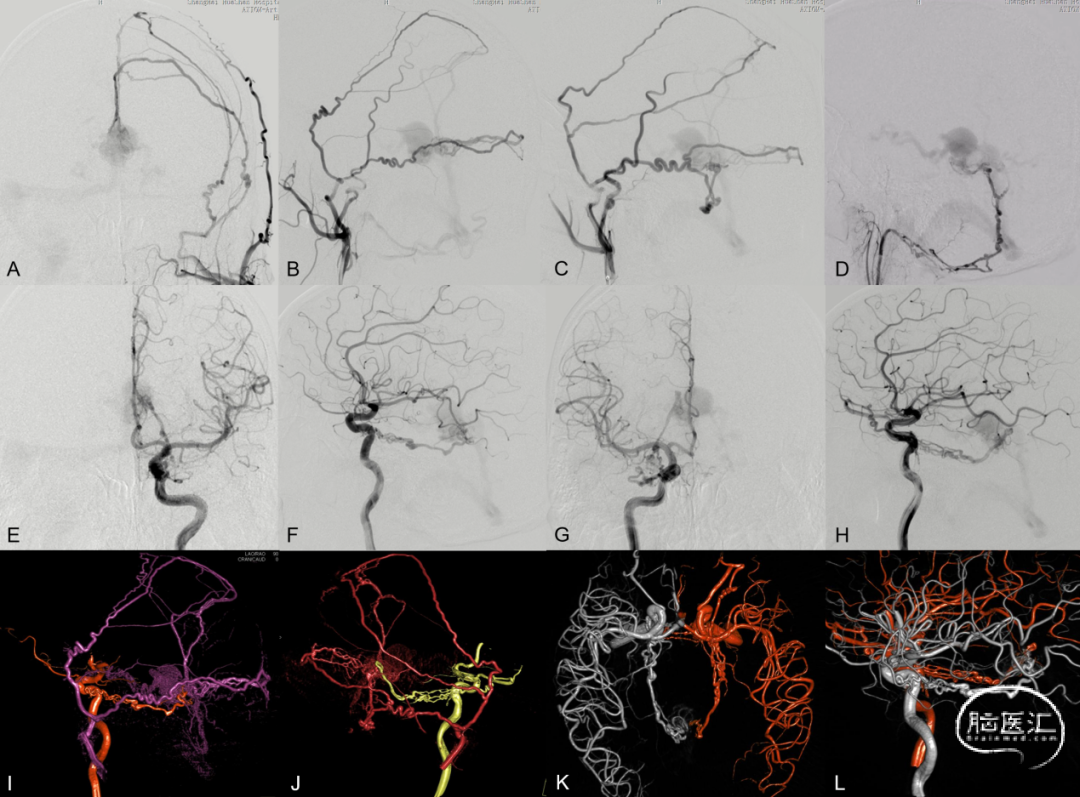

图14. 左侧颌内动脉 (A、B) 、右侧颌内动脉 (C) 、右侧咽升动脉 (D) 及双侧颈内动脉 (E-H) 造影示镰幕交界区硬脑膜动静脉瘘,供血动脉主要为双侧脑膜中动脉、右侧咽升动脉神经脑膜支及双侧脑膜垂体干,在Galen静脉处汇集,向深部静脉逆流并向直窦引流。DSA三维融合重建 (I-L): 左侧颈内颈外动脉融合 (I) 、右侧颈内颈外动脉融合 (J) 、双侧颈内动脉融合 (K、L) 显示静脉汇集区位于Galen静脉后部,此处即为栓塞治疗的靶区

图15. 侧窦区窦型DAVF典型血管构筑。初级硬膜静脉由脑膜中动脉(MMA)及枕动脉供血,向横-乙交界区血管汇集区(SP)(白箭)汇聚后进入静脉窦,乙状窦内间隔形成(A-C)。天幕岩部硬膜初级静脉向横-乙交界区SP汇集(双白箭),枕动脉血供经乙状窦垂直段SP(白箭头)进入静脉窦,并伴有上矢状窦(SSS)后部血栓形成(D-F)。DAVF经乙状窦颈静脉孔区SP(双白箭头)进入静脉窦并逆流,伴有乙状窦颈静脉孔段闭塞(G-I)

图16. 侧窦区桥静脉型DAVF典型血管构筑。MMA(白箭)、脑膜后动脉(双白箭)、大脑中动脉硬膜支(白箭头)及大脑后动脉硬膜支(黑双箭头)向Labbe桥静脉硬膜内段汇集(A-C)。MMA与颈内动脉(ICA),MMA与椎动脉,MMA与咽升动脉分别行双容积融合成像(D-F)。经动脉栓塞后Onyx胶在桥静脉及软膜静脉起始部的铸型(G)

图 17. 天幕缘组DAVF典型血管构筑。A-D:ECA发出的供血分支向天幕缘桥静脉(星号)汇集,经扩张的桥外侧静脉向对侧同名静脉引流。颌内动脉超选择造影(B)显示翼管动脉管径增粗,移行为硬膜静脉结构(双白箭)再汇入共同静脉端。F-G:TOF及增强磁共振、DAVF与颅骨的双容积融合成像显示桥静脉起始部(星号)位于岩尖的天幕游离缘。G:TAE后Onyx胶在桥静脉起始部的铸型

图 18. 上矢状窦区桥静脉型DAVF典型血管构筑。A-B:双侧MMA(单、双箭)向大脑上静脉桥静脉汇集。C:TAE后Onyx胶在硬膜动脉网(单、双箭)及桥静脉(双白箭头)的铸型。D:患者合并SSS中部血栓

图19. 髁前区DAVF典型血管构筑。A-C:枕动脉、咽升动脉供血分支向颈静脉结节静脉丛(JTVC)(白箭)汇集,经岩下窦向海绵窦、侧裂浅静脉逆流。D:ECA主干与咽升动脉双容积融合成像。E:位于骨内的JTVC(白箭)是髁前区板障-导静脉型DAVF的初级静脉结构。F:术中利用微导丝与静脉双容积融合成像定位。G-H:TVE闭塞JTVC及髁前静脉,治愈性栓塞DAVF同时保护岩下窦